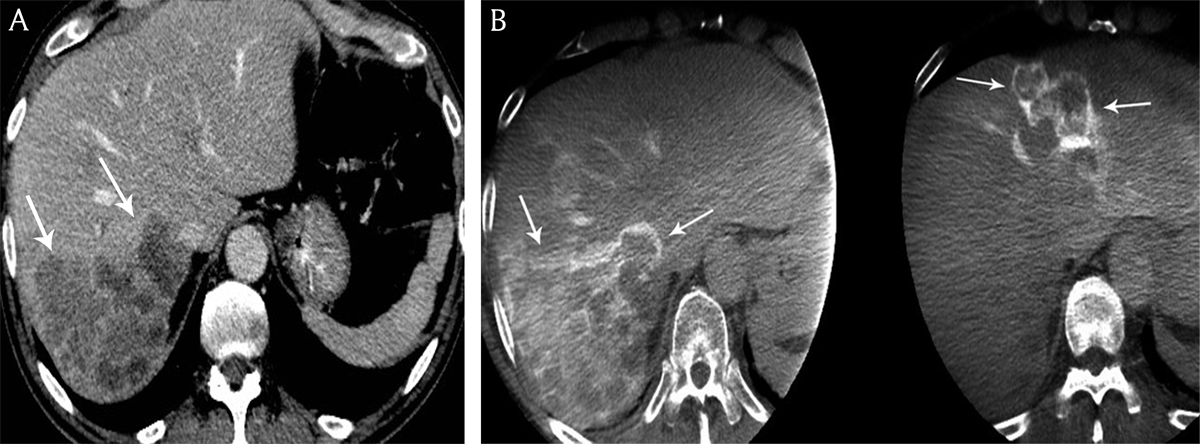

Figure 4

A) Contrast-enhanced computed tomography and B) cone beam computed tomography in a 68-year-old man presenting with bilobar colon cancer liver metastases. Contrast-enhancement of the peripheral tumoral rim is hyperdense to the residual liver parenchyma on cone beam computed tomography versus contrast-enhanced computed tomography.